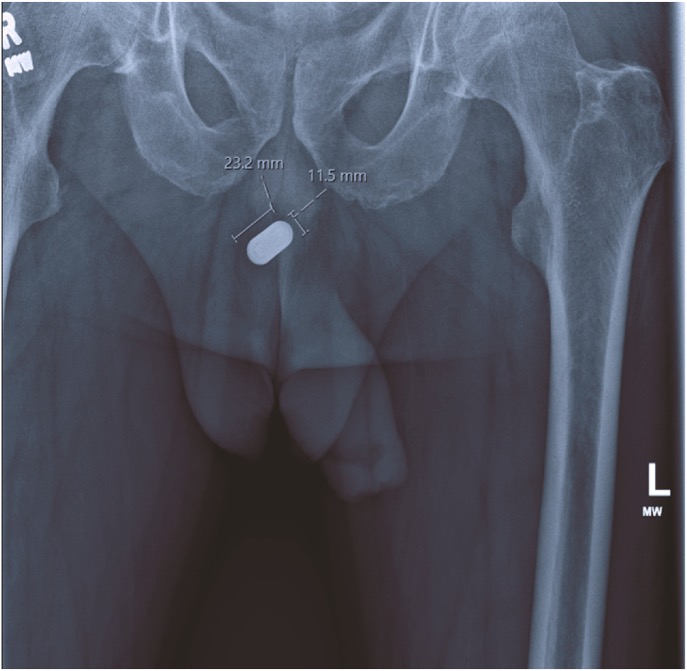

Figure 1. Rg таза показал инородное тело размером 23,2×11,5 мм в проксимальном отделе уретры.